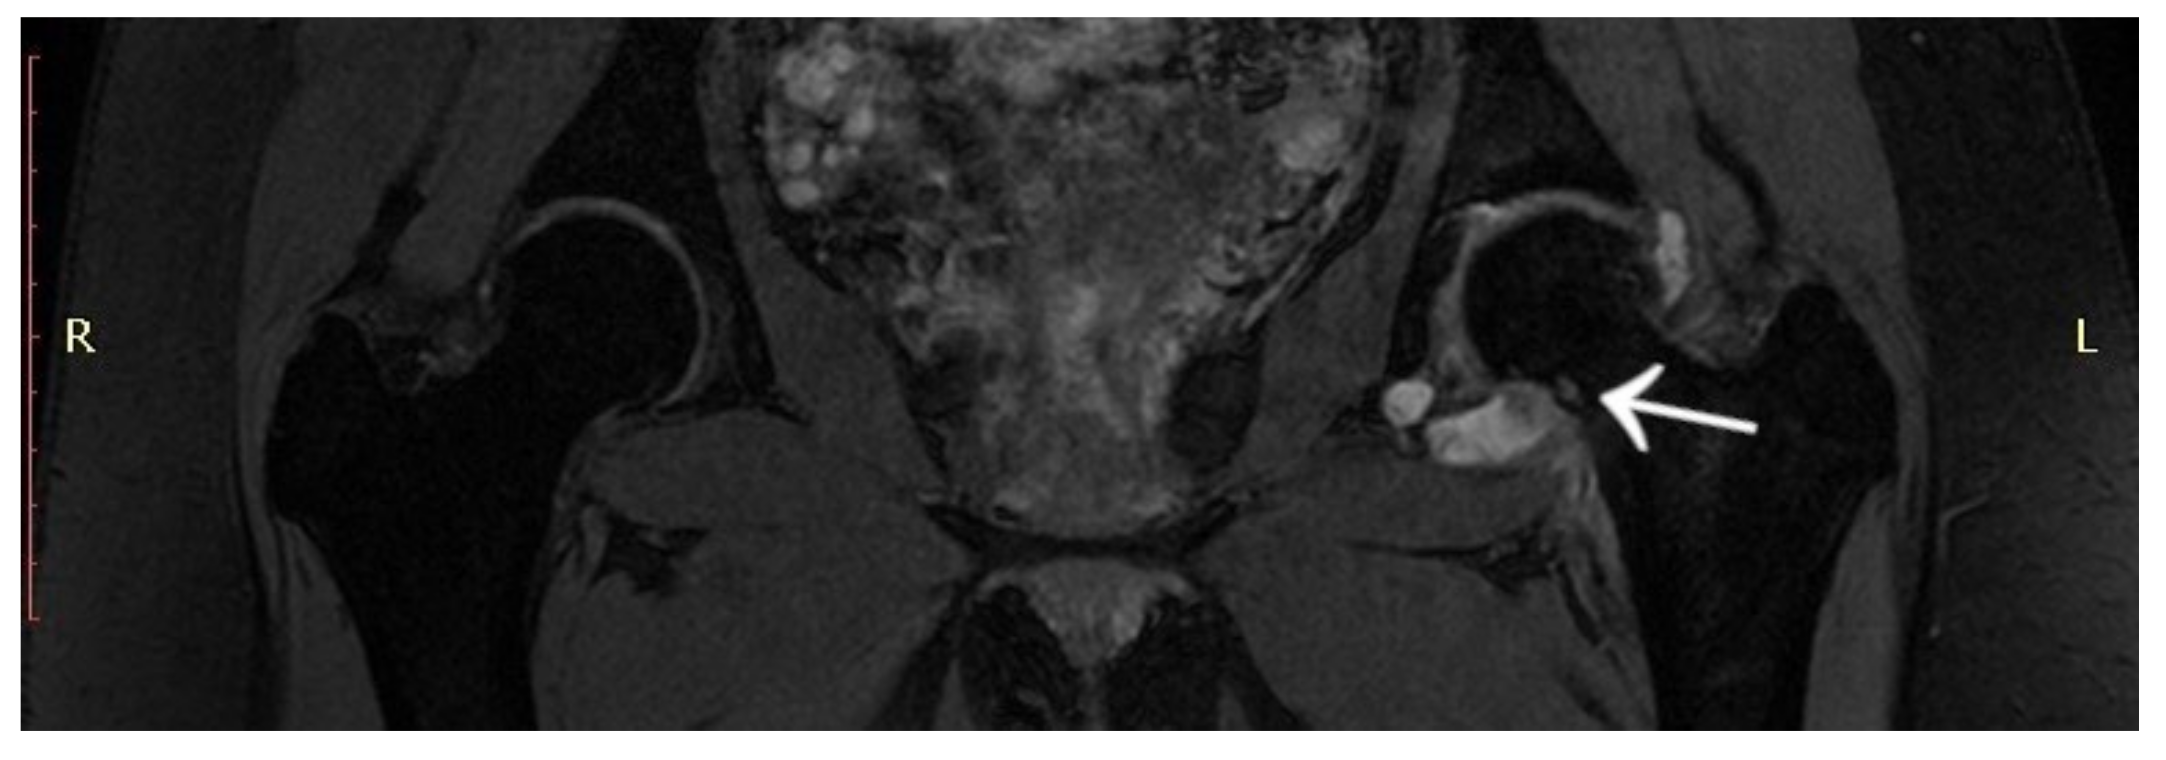

3.4. Case 4: OO Masking as a Fatigue Fracture